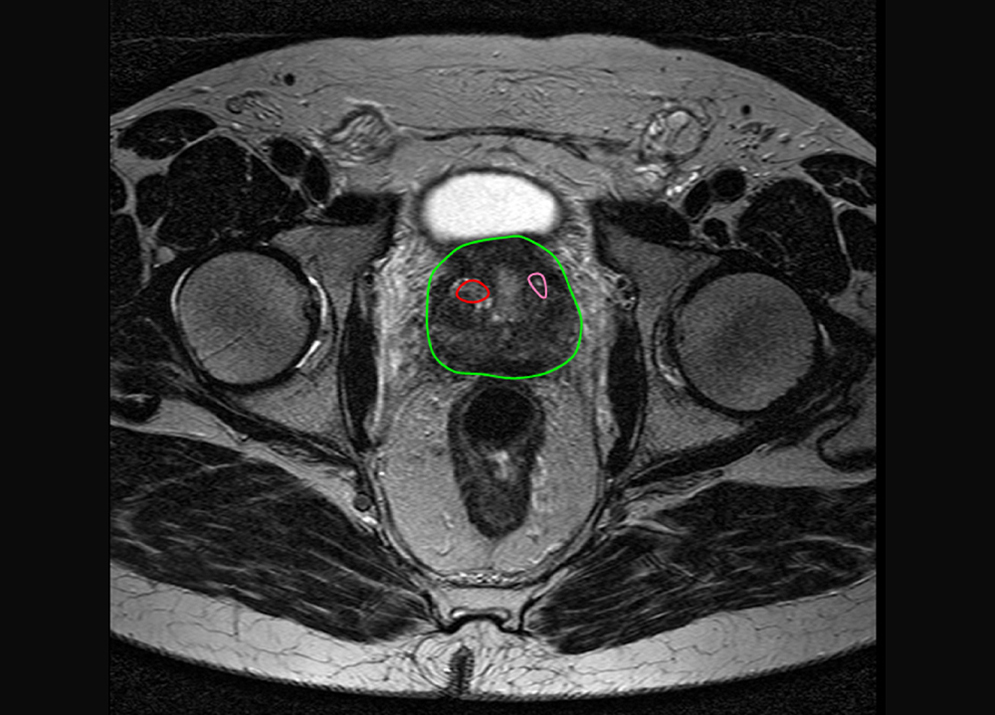

当院で導入した BioJet®システムによるMRI融合標的前立腺生検 では、事前に撮影したMRI画像で「がんの疑いがある部位」を解析し、その情報を生検時の超音波画像と融合(フュージョン)させて3Dで表示。針を刺すべき部位を正確にナビゲーションし、ピンポイントで組織を採取できます。

針で組織を採取するMRIフュージョン生検のイメージ。赤と薄橙の部分が、がんが疑われる場所

高性能なナビゲーションシステムによりピンポイントでの採取が可能